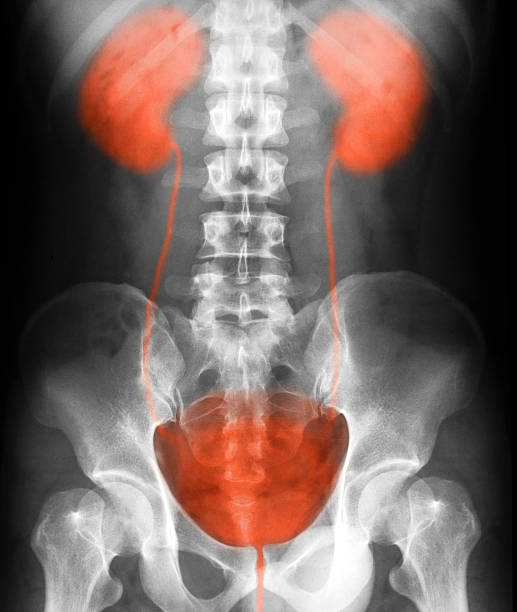

x-ray image of the urinary tract:

Supine Position Of Urinary Tract Xray Image Stock Photo – Download …

Plain Kub Or Xray Image Of Urinary System Showing Kidney And Bladder …